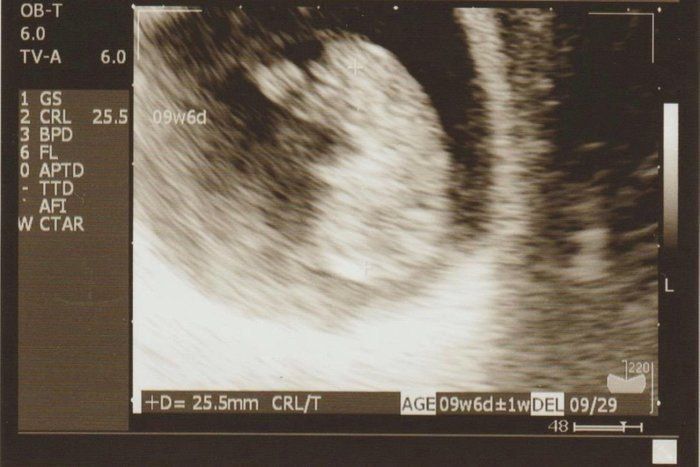

チャーミー小結さんの妊娠9週目のエコー写真

何となく頭と胴体の区別が出始め、胎芽から胎児とよばれるようになりました。スリムな人だとまだおなかの膨らみが分からない頃ですが、嬉しくてウエストノーマークのマタニティ服を着て過ごしていました。